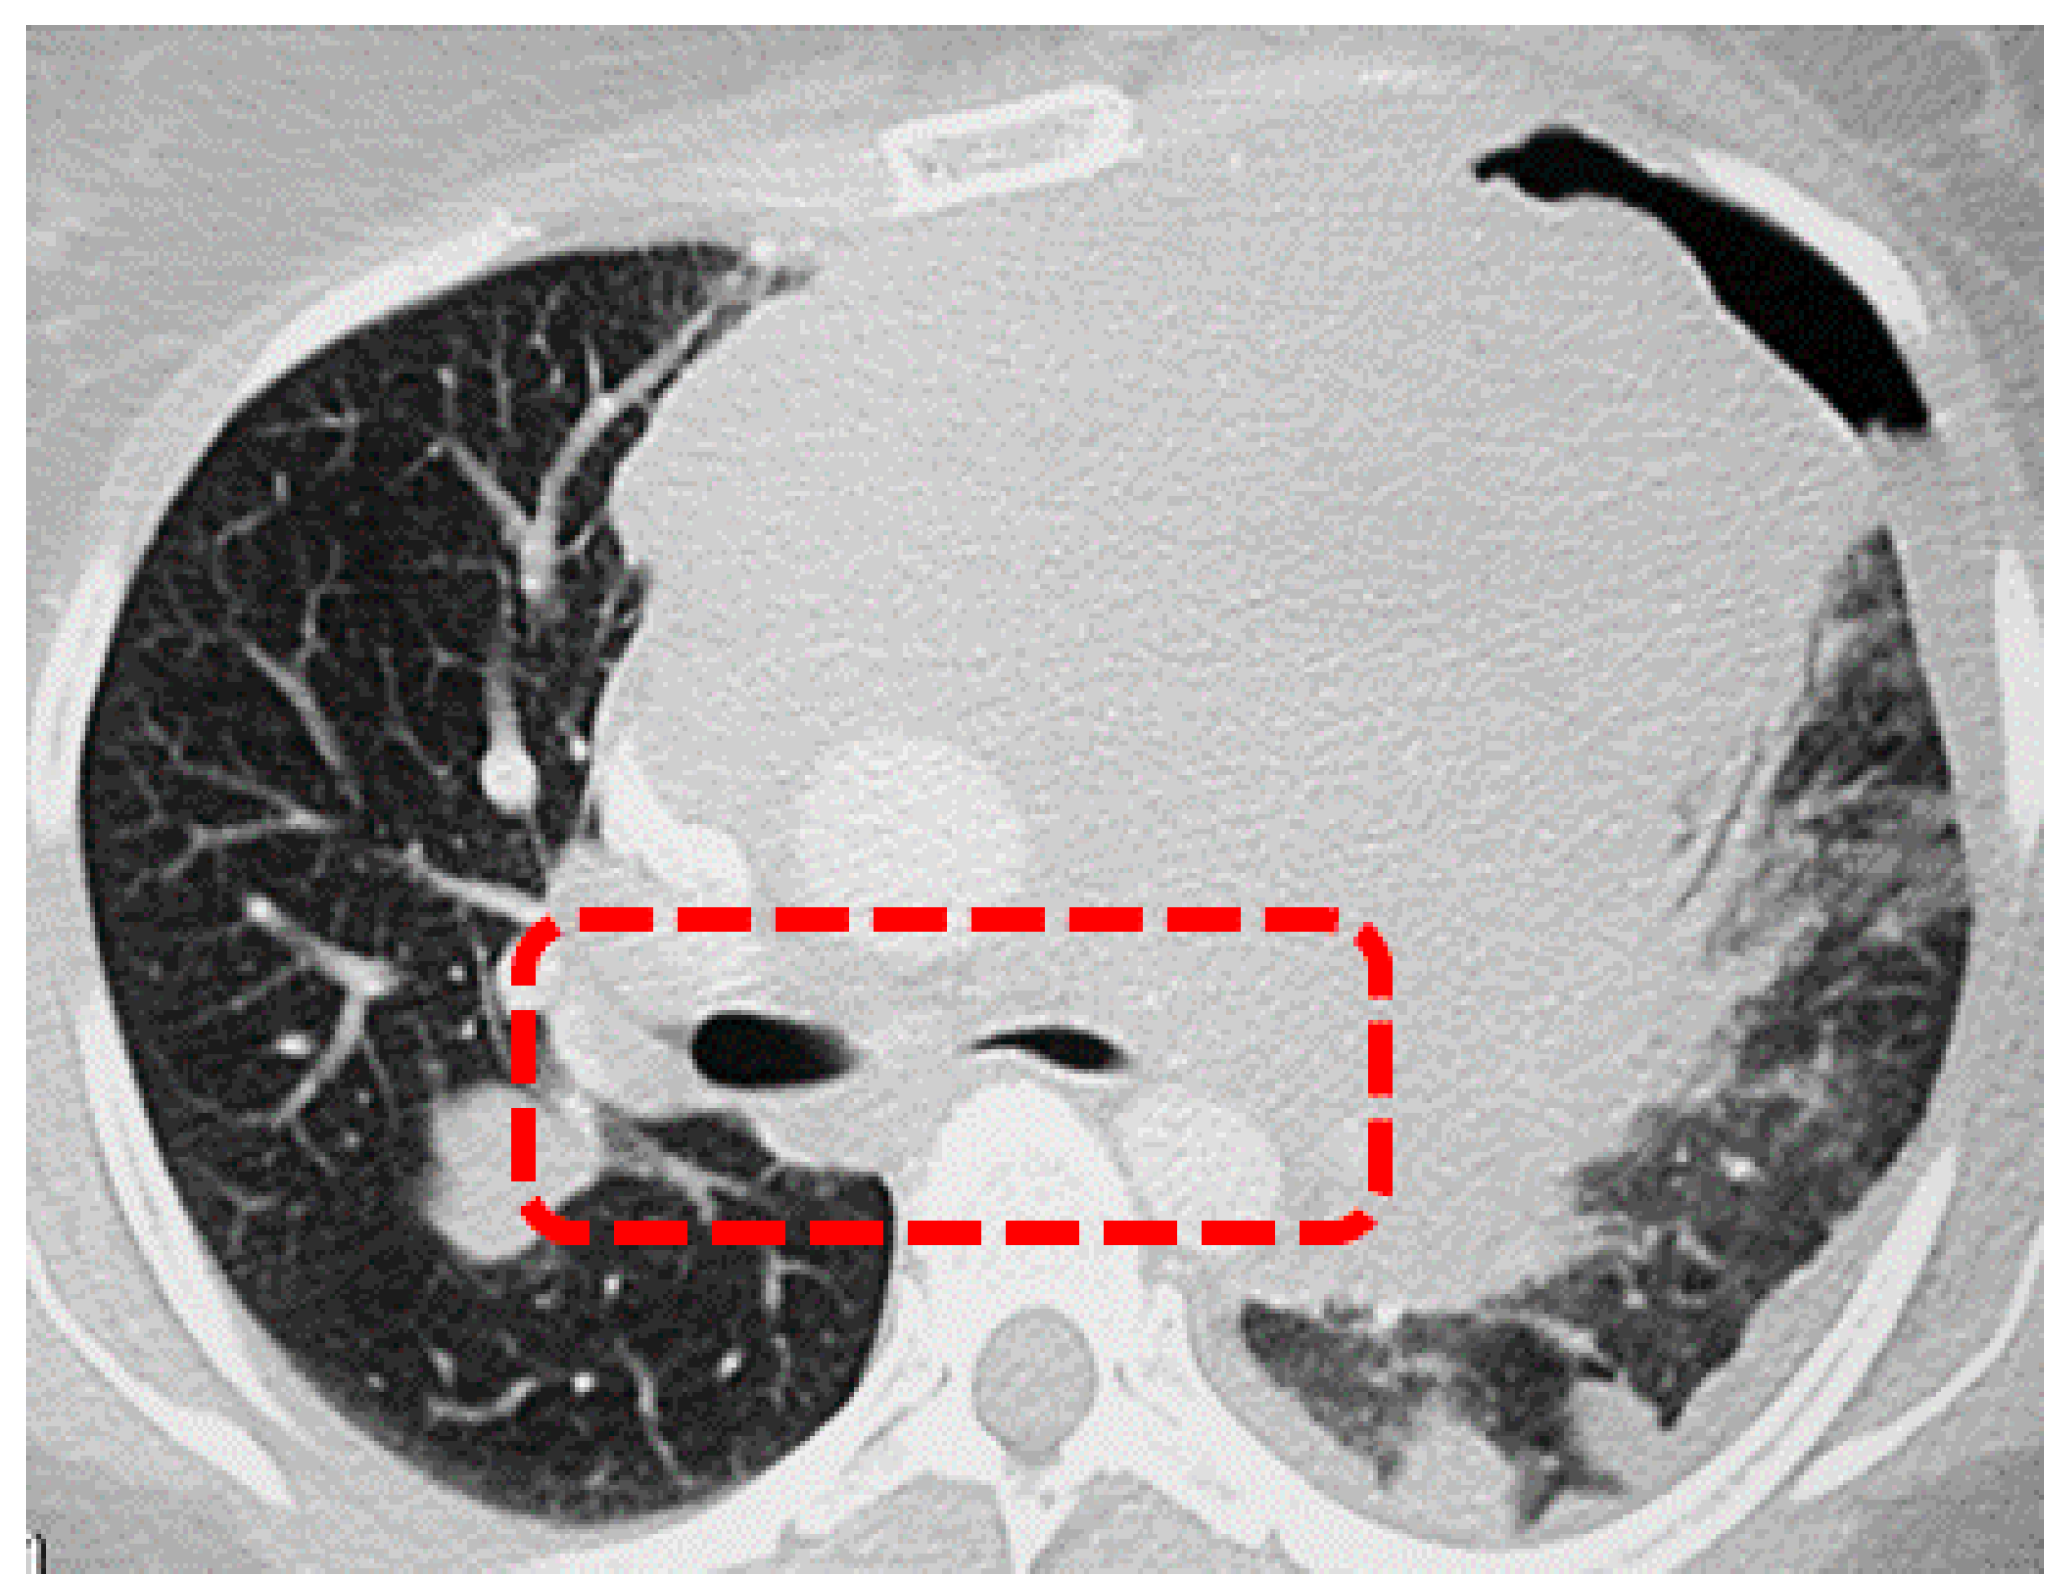

| First Author | Year | Country | Study Design | Number of Patients | Surgical Access | Comparison with MV-VATS (SV vs. MV) | MG Patients |

|---|---|---|---|---|---|---|---|

| Hartert [18] | 2022 | Germany | Case series | 3 | Subxiphoid | No | Yes |

| Liu [19] | 2021 | China | Case series | 10 | Subxiphoid | No | Yes |

| Huang [20] | 2020 | China | Retrospective | 32 | Triportal | Yes (15 vs. 17) | No |

| Mao [21] | 2020 | China | Retrospective | 40 | Subxiphoid | Yes (21 vs. 19) | Yes |

| Liang [22] | 2019 | China | Retrospective with PSM | 198 | Biportal | Yes (55 vs. 55) | Yes |

| Liu [23] | 2019 | China | Retrospective | 225 | Uniportal | Yes (96 vs. 129) | No |

| Jiang [24] | 2018 | China | Retrospective | 104 | Triportal | Yes (36 vs. 68) | Yes |

| Pompeo [25] | 2017 | Italy | Case series | 3 | Uniportal | No | Yes |